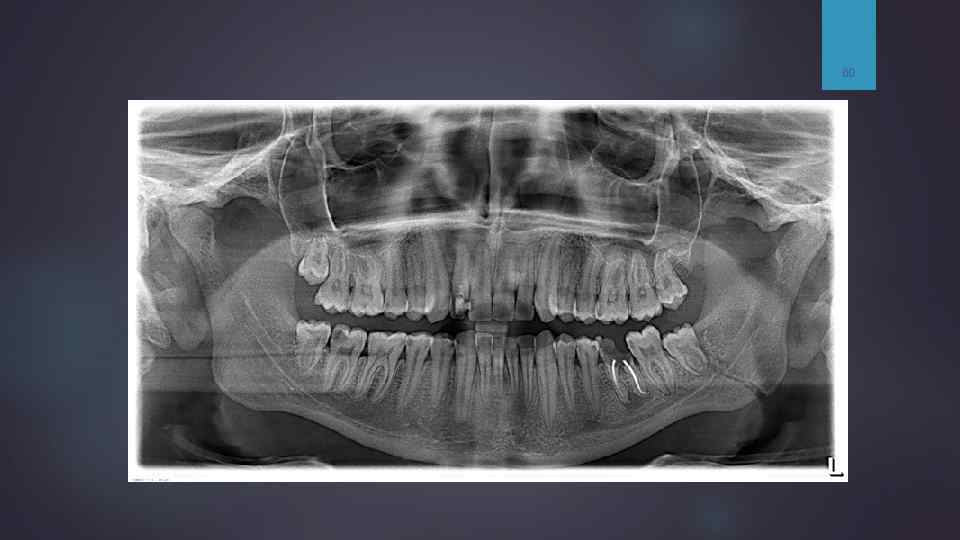

Ортопантомограмма. Двусторонний перелом тела нижней челюсти — линия перелома справа проходит между 6 и 5, слева — в области угла. Отломок смещен вертикально.

60